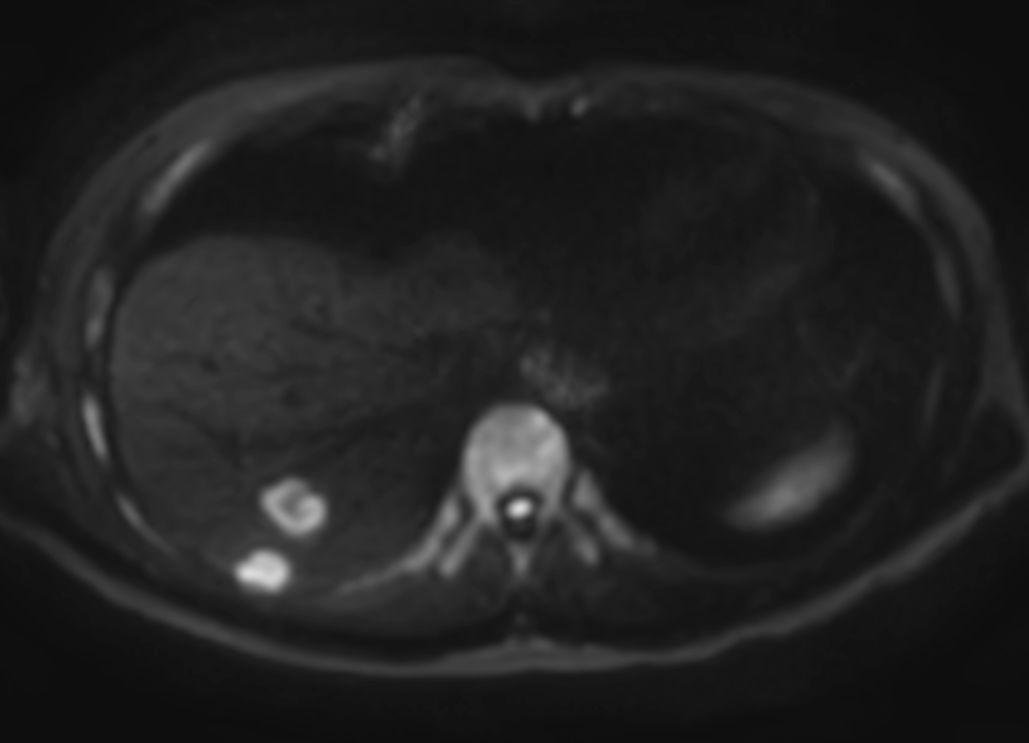

Liver metastasis – Free breathing

Patient with liver metastasis. ExamCard includes Compressed SENSE to shorten the breath hold time, VitalEye for touchless respiratory sensing, mDIXON Quant for non-invasive liver fat fraction quantification and 4D FreeBreathing to perform multi-phase contrast-enhanced MRI studies.

Diffusion b1000 - Free Breathing (VitalEye)

Diffusion b1000 (ADC) - Free Breathing (VitalEye)